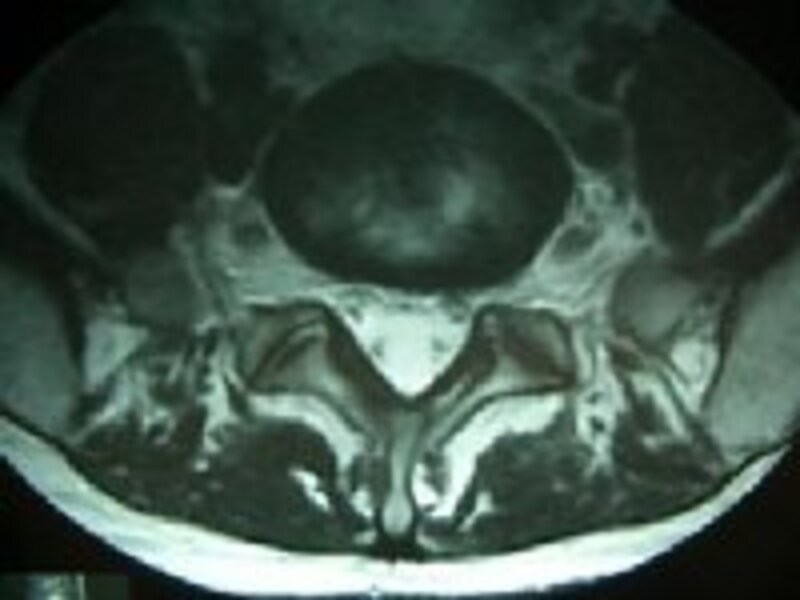

右の写真をご覧下さい。上の写真は背中を横からみた状態(左がおなか側)、下の写真は体を輪切りにした状態(上がおなか側)です。

MRIではいろいろなことがわかります。特に一番わかりやすいのは腰の神経の状態です。右の写真で、竹のように見える骨の後ろにある、黒い球根の根のような形のものが『脊髄神経』といわれる神経です。この神経がさまざまな理由で圧迫されて炎症をおこすと、神経痛が生じます。

| 横断面 |

ちなみに上のMRIをもう一度ごらん下さい。下の方の椎間板は上の方の椎間板に比べてやや黒くなって少しつぶれてますよね。これが『椎間板の変性』です。ただし、これは普通のヒトでも良く起こりますし、病的とも限りません。(このMRIは実はガイド自身のものだったりします)